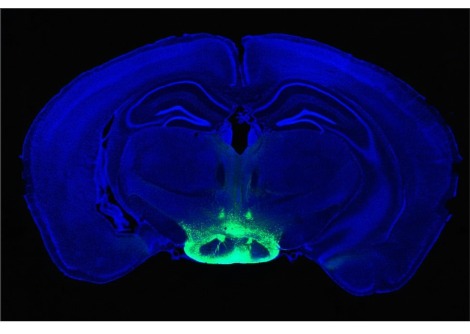

تتأثر آلام أسفل الظهر بالعديد من العوامل ، بما في ذلك البيولوجية والاجتماعية والنفسية . يعني التعقيد التشريحي للعمود الفقري البشري أنه في معظم الحالات ، لا يمكن تحديد سبب بنيوي بسيط مثل مفصل أو عضلة واحدة ، حتى مع التصوير التشخيصي المتطور.